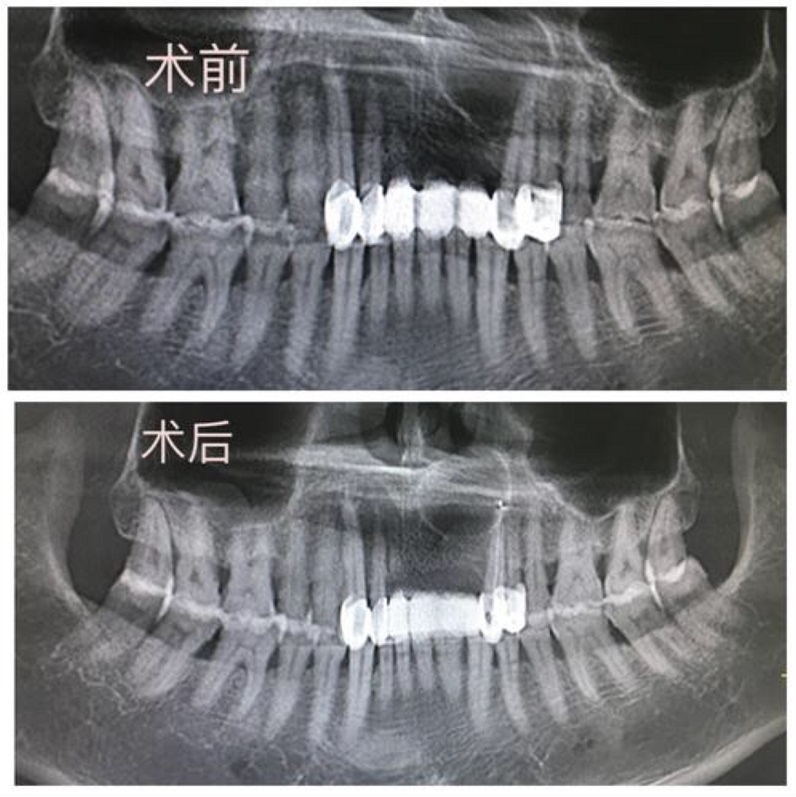

术前术后曲面断层片对照